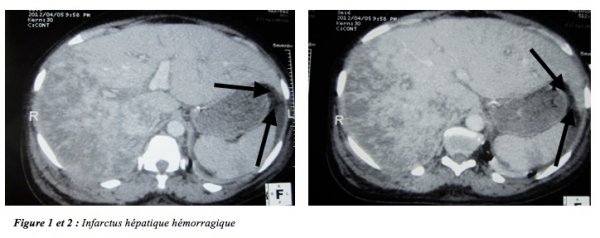

Un avis gynécologique demandé avait objectivé un abdomen souple, avec des bruits du cœur fœtal perceptible au Dopton, et des leucorrhées fétides au toucher vaginal. Le premier bilan biologique avait retrouvé une légère anémie à 11,2g/dl d’hémoglobine, une thrombopénie à 95000/mm3, une cytolyse majeure avec un taux d’aspartate amino-transférase (ASAT) à 2165 UI/l et d’alanine amino-transférase (ALAT) à 1219UI/l, une légère altération de la fonction rénale avec un taux d’urée à 8,3 mmo/l/l et une créatinine à 176 µmol/l. La goutte épaisse était négative de même que la recherche d’un portage chronique d’hépatite B ou C. Le diagnostic de HELLP syndrome surajouté a été évoqué. Par ailleurs nous n’avions pas pu rechercher la présence de schizocytes ni doser les lactico-déshydrogénases (LDH). Les premières mesures thérapeutiques avaient consisté à la prise en charge de l’hypertension artérielle par des inhibiteurs calciques en intraveineuse continue et un traitement des crises convulsives par du sulfate de magnésie. Au deuxième jour d’hospitalisation, devant l’absence de maîtrise des chiffres tensionnels, l’apparition d’une anurie totale, l’aggravation de la cytolyse et de la thrombopénie jusqu’à 40000/mm3 une interruption de la grossesse a été décidée en accord avec les gynécologues. Celle-ci devait se faire par un déclenchement par voie basse avec du Misoprostol (Cytotec® 50µg) toutes les 6 h en intra vaginal ce qui a permis l’expulsion de deux mort-nés macérés de sexe masculin. Une antibioprophylaxie associant amoxicilline et acide clavulanique a été instaurée, associée à une tentative de relance de la diurèse par un remplissage et l’utilisation du furosémide en intraveineuse. Au dixième jour de prise en charge devant l’aggravation de la fonction rénale (urée à 33,2 mmol/l et créatinine à 560 µmol/l) et hyperkaliémie à 6,1 mmol/l associée à une douleur abdominale intense, une tomodensitométrie (TDM) abdominale injectée a été demandée pour éliminer un hématome sous capsulaire du foie rompue ou une péritonite. Cette dernière avait mis en évidence un infarctus hépatique hémorragique et une ascite de moyenne abondance (figure 1 et 2). Une séance d’épuration extra-rénale avait été nécessaire pour relancer la fonction rénale.

L’infarctus hépatique hémorragique au cours d’une pré-éclampsie compliquée se voit rarement. C’est la complication hépatique la moins rencontrée au cours de la pré-éclampsie [3]. Il est le plus souvent associé à un HELLP syndrome et survient habituellement tard au cours de la grossesse [2,4]. Dans le cas que nous rapportons, la pré-éclampsie a été d’abord compliquée d’éclampsie et de HELLP syndrome puis d’une altération de la fonction rénale et d’un infarctus hépatique hémorragique. Dans la littérature, l’altération de la fonction rénale n’est pas forcément associée au tableau clinique [2,4]. Les manifestations cliniques sont trompeuses, d’où la nécessité d’une surveillance para clinique approfondie. Les bilans biologiques réalisés avaient montré des taux de transaminases nettement supérieurs à la normale comme décrit dans certaines études [5] et une thrombopénie sévère concluant ainsi à un HELLP syndrome. Devant l’apparition des complications viscérales et la non-maitrise des chiffres tensionnels, l’arrêt de la grossesse a été décidé comme décrit dans certaines études [6]. Le diagnostic de l’infarctus hépatique hémorragique a été retenu après la réalisation d’une tomodensitométrie abdominale. L’imagerie notamment la tomodensitométrie et l’échographie abdominale restent les examens de références pour poser le diagnostic de cette affection [4,2,7]. L’attitude thérapeutique reste la surveillance clinique et biologique. Dans notre cas, l’évolution a été marquée par la régression des lésions hépatiques sans séquelle comme rapporté par certains auteurs [2].